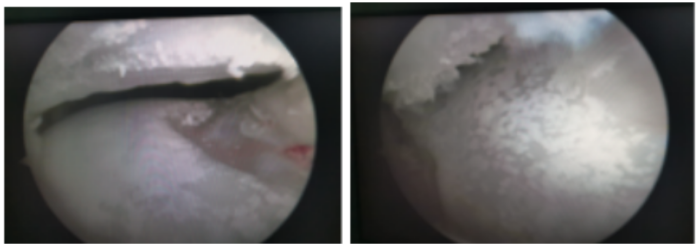

)运动医学、关节、骨病科就诊,完善相关检查后,发现他并不是简单的扭伤。后仔细询问病史才发现李先生以前就有尿酸增高的病史,由于一直没有症状,所以就没有引起重视,所以,这次扭伤成了他痛风发作的诱因,目前,李先生已经顺利接受了关节镜术,镜下看到他的软骨上面一层厚厚的“石灰”,经处理伤口恢复良好,关节功能恢复满意。

(关节镜下看到患者的软骨上面一层厚厚的“石灰”)